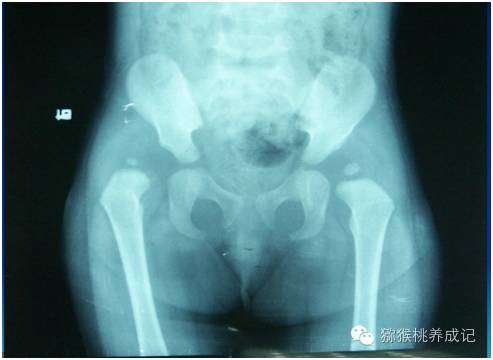

图为右侧髋关节脱位

发育性髋关节发育不良(DDH)又称发育性髋关节脱位,是儿童骨科最常见的髋关节疾病,发病率在1‰左右,女孩的发病率是男孩的5倍左右,左侧约为右侧的2倍,双侧约占35%。DDH包括髋关节脱位、半脱位和髋臼发育不良,较以往“先天性髋关节脱位”的名称更能够代表该病的全部畸形。

髋关节主要是由髋臼和股骨头组成,它们的结构就像杵臼,髋臼就是臼,股骨头就是杵。不同的是髋关节有关节囊和韧带把杵固定在臼之中,DDH发病就是由于种种原因,杵没能固定在臼之中,而是可以滑动,跑到臼外去。